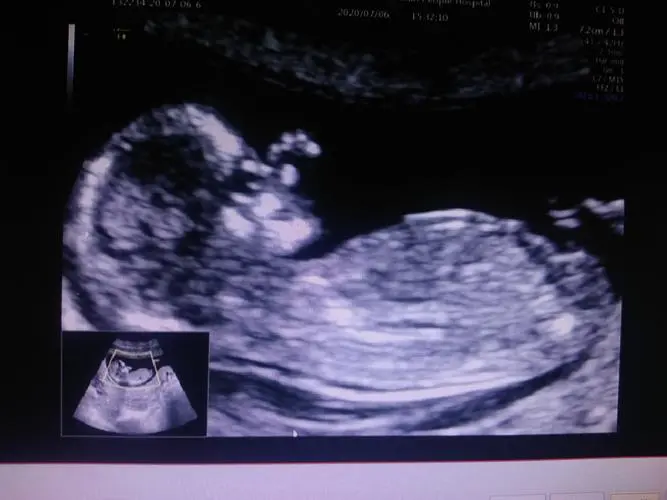

NT检查,即颈后透明带扫描,是一种通过超声波检查胎儿颈后透明层的厚度来评估胎儿是否存在染色体异常风险的检查方法。通常在孕期的11-13周+6天进行,此时胎儿的颈后透明层最为明显。

早孕期胎儿颈后部皮下会有液体聚积,在超声检査中呈现为特征性的无回声区,即颈项透明层,通过测量无回声区来反应的颈项透明层厚度。

NT检查,全称为NT彩超检查,属于彩超检查项目之一。它通过测量胎儿颈部透明带的厚度来评估胎儿可能患有唐氏综合征和其他畸形的风险。通常,颈项透明层越厚,胎儿存在异常的概率就越大。这种检查通常在孕期的第11-13周进行,旨在了解胎儿的生长发育情况以及是否存在发育异常或畸形。

当NT的厚度超过正常范围,即3毫米,并且数值越大时,意味着胎儿出生后患病的几率也相应增大。怀孕的第11-13周是进行NT检查的最佳时机。一旦怀孕超过14周,NT会逐渐被胎儿体内的淋巴系统吸收,转变为颈部褶皱,此时便无法再进行测量。